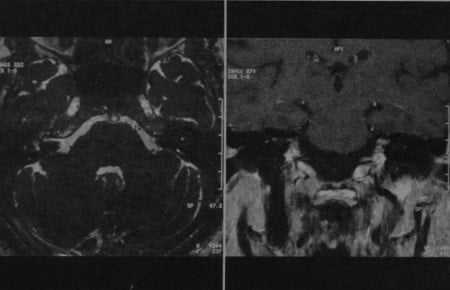

(Слева) При аксиальной МРТ Т1 ВИ С+ FS на уровне внутренних слуховых каналов определяется нормальное контрастное усиление коленчатого ганглия и переднего барабанного сегмента ЧН VII слева. Справа определяется нормальное контрастное усиление переднего барабанного сегмента.

(Справа) При аксиальной MPT Т1 ВИ С+ FS у пациента с правосторонней вестибулярной шванномой определяется повышенное контрастирование лабиринтного, переднего тимпанического сегмента ЧН VII, и коленчатого ганглия.

(Слева) При корональной МРТ Т1 ВИ С+ FS на уровне преддверий определяется нормальное контрастирование среднего барабанного сегмента лицевых нервов.

(Справа) При корональной МРТ Т1ВИ С+ FS у этого же пациента определяется нормальное контрастирование коленчатого ганглия сразу же над улиткой. Обратите внимание на мышцы, напрягающие барабанную перепонку, накапливающие контраст с обеих сторон. При ЗТ нормальное контрастное усиление структур височной кости более выражено.